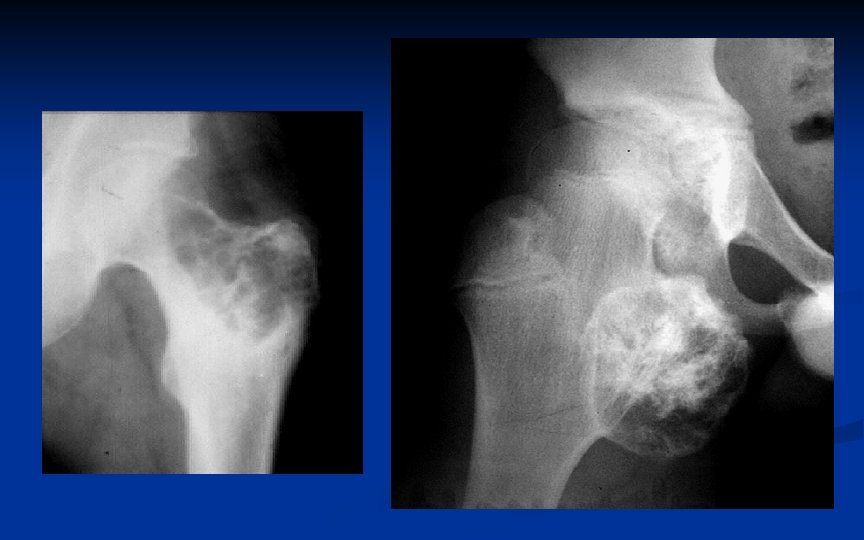

CONDROSSARCOMA Cerca de 9% das neoplasias primárias do osso (50% do osteossarcoma) Pico entre 40 -60 a para o primário e 25 -45 a para o secundário Pelve, fêmur e úmero proximal. Mesmo raro na mão, é a neoplasia maligna mais comum deste local

CONDROSSARCOMA RX Lesão surgindo da medular com calcificação irregular da matriz (aspecto pipoca) Alguma destruição óssea, erosão cortical reação periosteal e raramente massa partes moles (TC é útil para evidenciar estas características) Se capa cartilaginosa >2 cm na TC ou RNM suspeitar de condrossarcoma